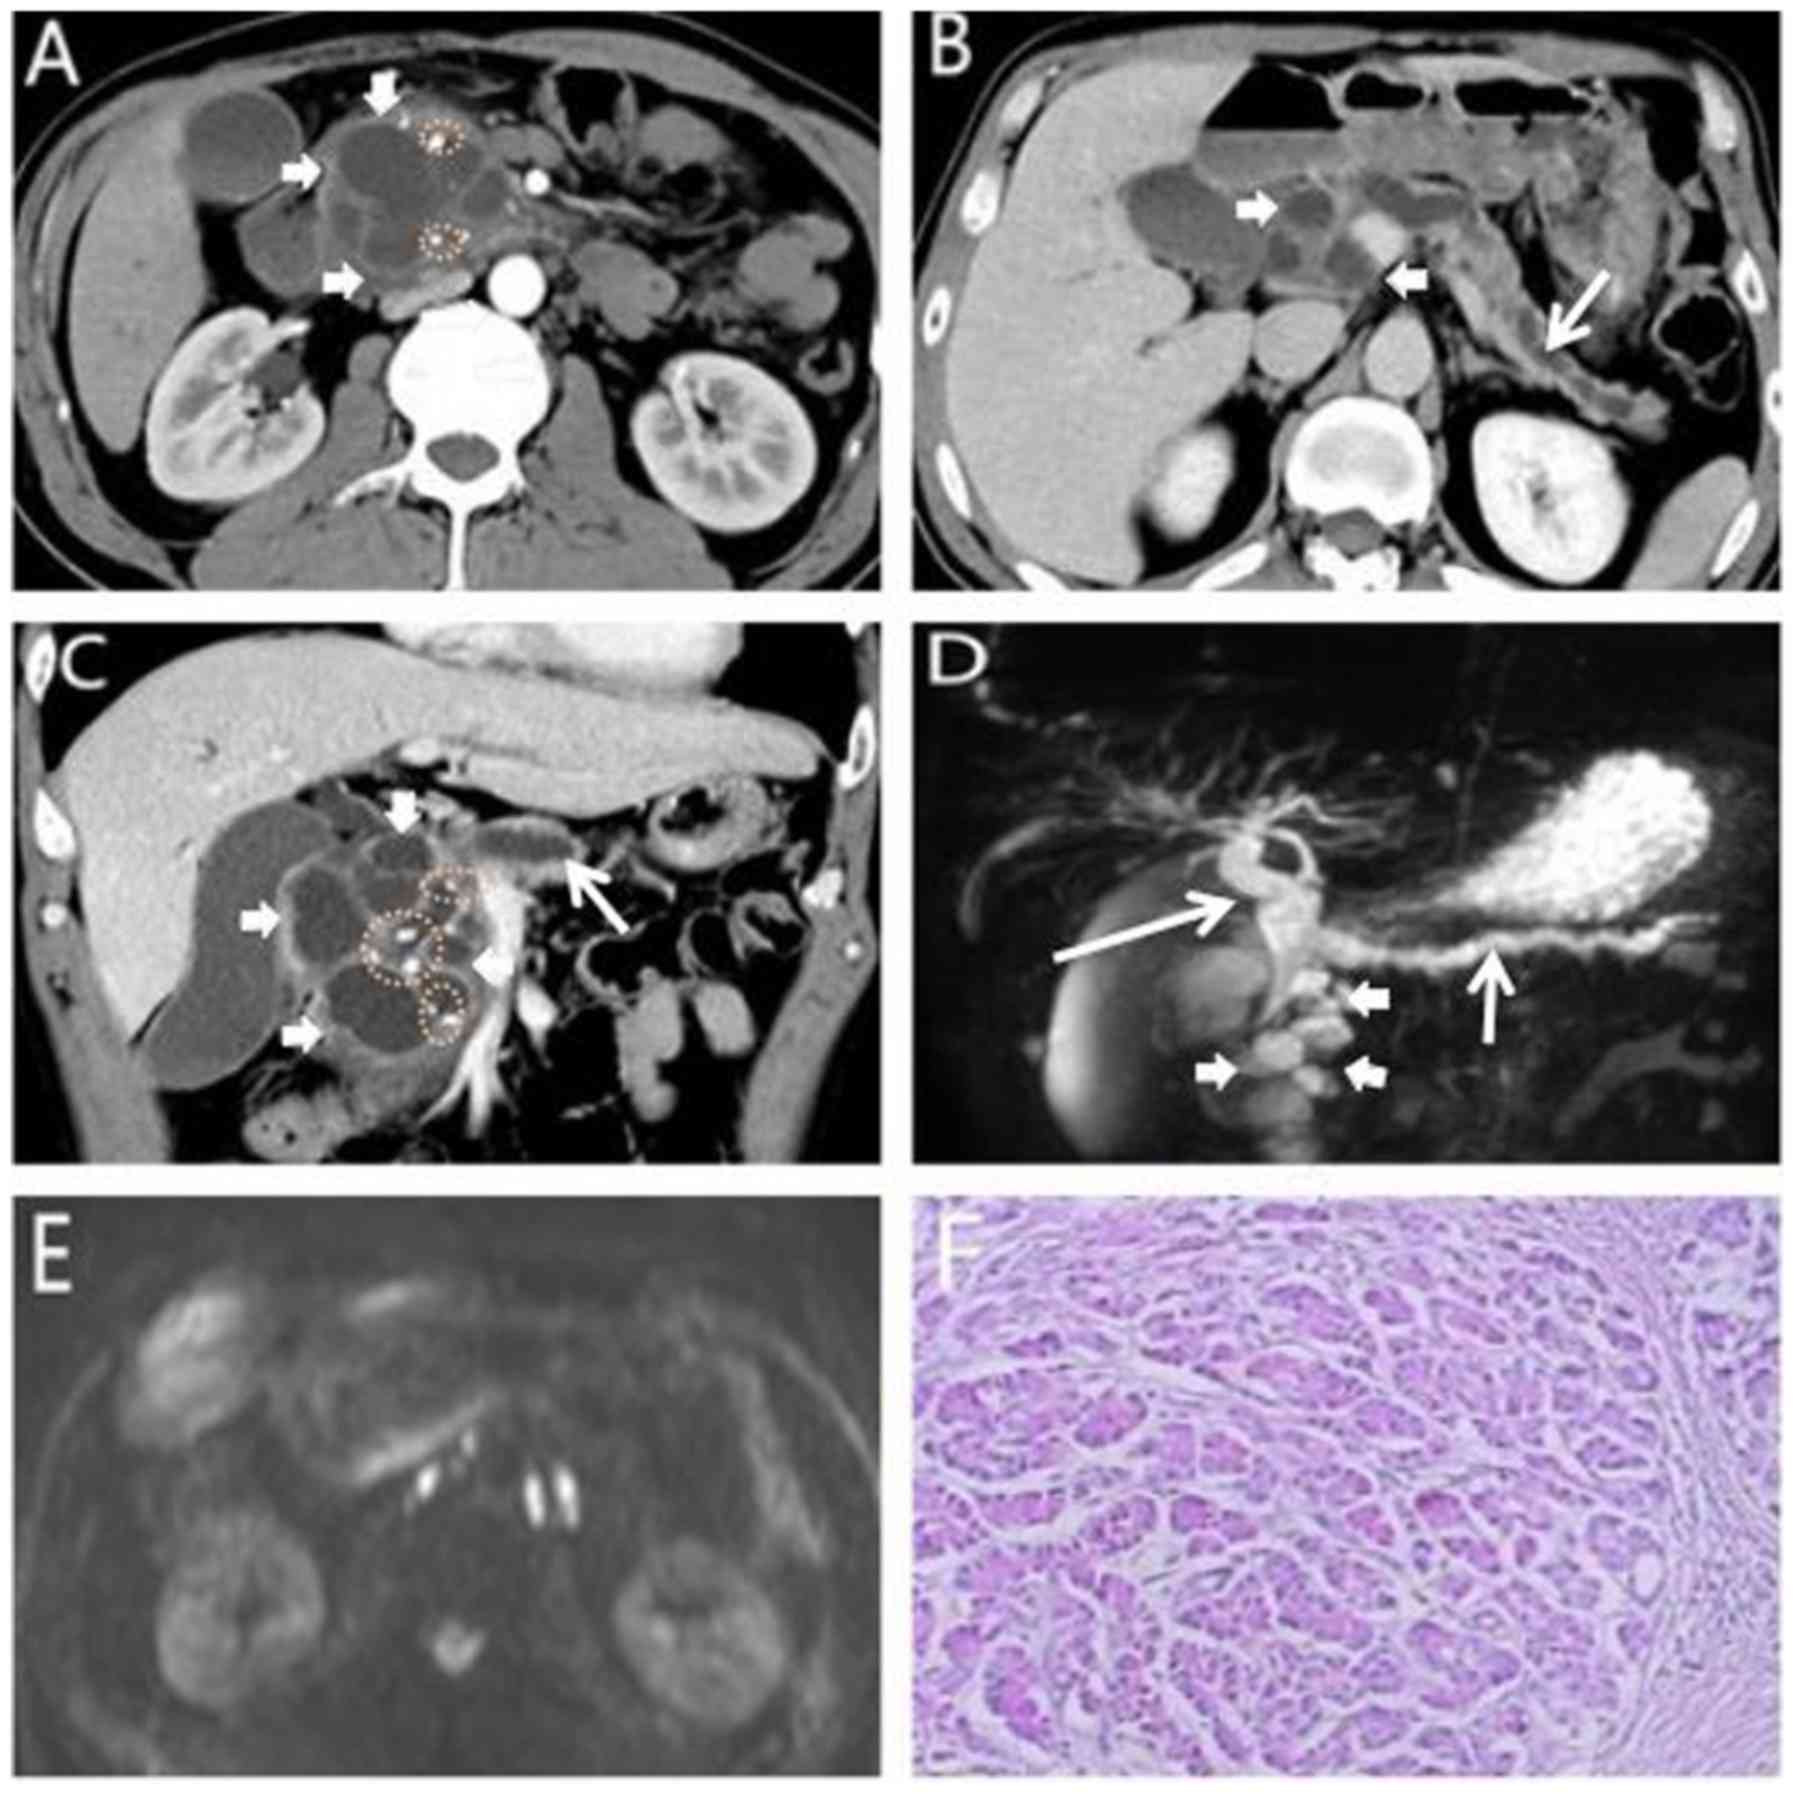

Successful Treatment Of A Locally Advanced Unresectable Pancreatic